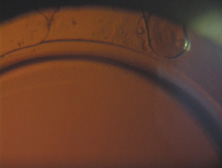

Because of these compounding developments, David Apple began his important work with Randy Olson and in 1983 founded the Center for Intraocular Lens Research at the University of Utah. They were a uniquely qualified combination. Dr. Apple was board certified as both a pathologist and ophthalmologist; Dr. Olson was an academic ophthalmic surgeon. Much like Harold Ridley and Peter Choyce, they began their dedicated quest to improve the condition of pseudophakia. They solicited autopsy specimens and wrote innumerable articles about IOL design, centration, and complex IOL–ocular interactions. One of their most important articles, published in 1985, was a position article citing the advantages of capsular bag placement and recommending it over ciliary sulcus placement, still a controversial issue at the time.44 The eyes submitted to them that year demonstrated capsular bag fixation in 31%, ciliary sulcus fixation in 11%, and asymmetric bag–sulcus fixation in 58%.45 At that time, 85% of surgeons still preferred planned ECCE as their surgical technique.46 While in Utah, Apple and Olson saw the problems created by ARTs solved with the invention of capsulorrhexis, almost simultaneously reported in 1986 by four surgeons from around the world. Two presented articles at the Welch Cataract Congress in Houston that year, and two reported their techniques independently. The discovering surgeons in alphabetical order are Drs. Calvin Fercho (Welsh Cataract Congress, Houston, 1986), Howard Gimbel (video presentation at the annual meeting of the ASCRS in Boston, 1985),47 John Graether (Welch Cataract Congress, Houston, 1986),48 and Thomas Neuhann (video presentation at the meeting of the German Ophthalmological Society in Heidelberg, 1985).47 With this technique, and the creation of an approximate diameter of 5 mm, symmetric placement of any IOL could be guaranteed. It still took several years for the majority of ophthalmologists to incorporate continuous curvilinear capsulorrhexis (CCC) into their surgical routines. In 1988 Dr. Apple relocated the laboratory to the Storm Eye Institute at the Medical University of South Carolina in Charleston. Reflecting new challenges, his laboratory name would be changed to the Center for Research on Ocular Therapeutics and Biodevices. From there, he and his staff, residents, and research fellows continued to receive autopsy specimens from around the world and eventually demonstrated, in the largest autopsy specimen study to date, a decline in asymmetric placement to only 10% of eyes with foldable lenses submitted in 1998.45 Early in his work there, Dr. Apple recruited Dr. Kensaku Miyake's retrociliary photographic analysis method to locate and analyze IOL placement within the eye (Fig. 18). With increasing video sophistication and use of the process by Dr. Apple and his colleagues, Dr. Miyake himself generously expanded the name of the procedure to be called the Miyake-Apple technique. After cancer was diagnosed in Dr. Apple and he was successfully treated, the center was relocated to Salt Lake City in 2002, where it has been permanently designated as the David J. Apple, MD, Laboratories for Ophthalmic Devices Research. In the days when the laboratory was in Charleston, Dr. Apple worked with industry representatives and surgeons to refine IOL design to ensure that capsular bag residence would be as consistent as possible, thereby reducing lens contact with other eye structures in both routine and complicated situations (Figs. 19 and 20). J.A.D. had the great pleasure of working with him in his laboratory to help improve an already sophisticated haptic configuration in a one-piece all-PMMA IOL. At that time, we thought that the entire haptic should be C-shaped so that even its distal end could be recruited for capsular equatorial support (Fig. 21). We studied resistance to haptic compression, attempting to make it softer and more uniform through diameter reductions from 13.0 to 11.5 mm 2.5 mm (Fig. 22). These efforts contributed to the development of the Pharmacia model 811, which, along with others of its day, may have represented the height of single-piece PMMA IOL development (Fig. 23).49